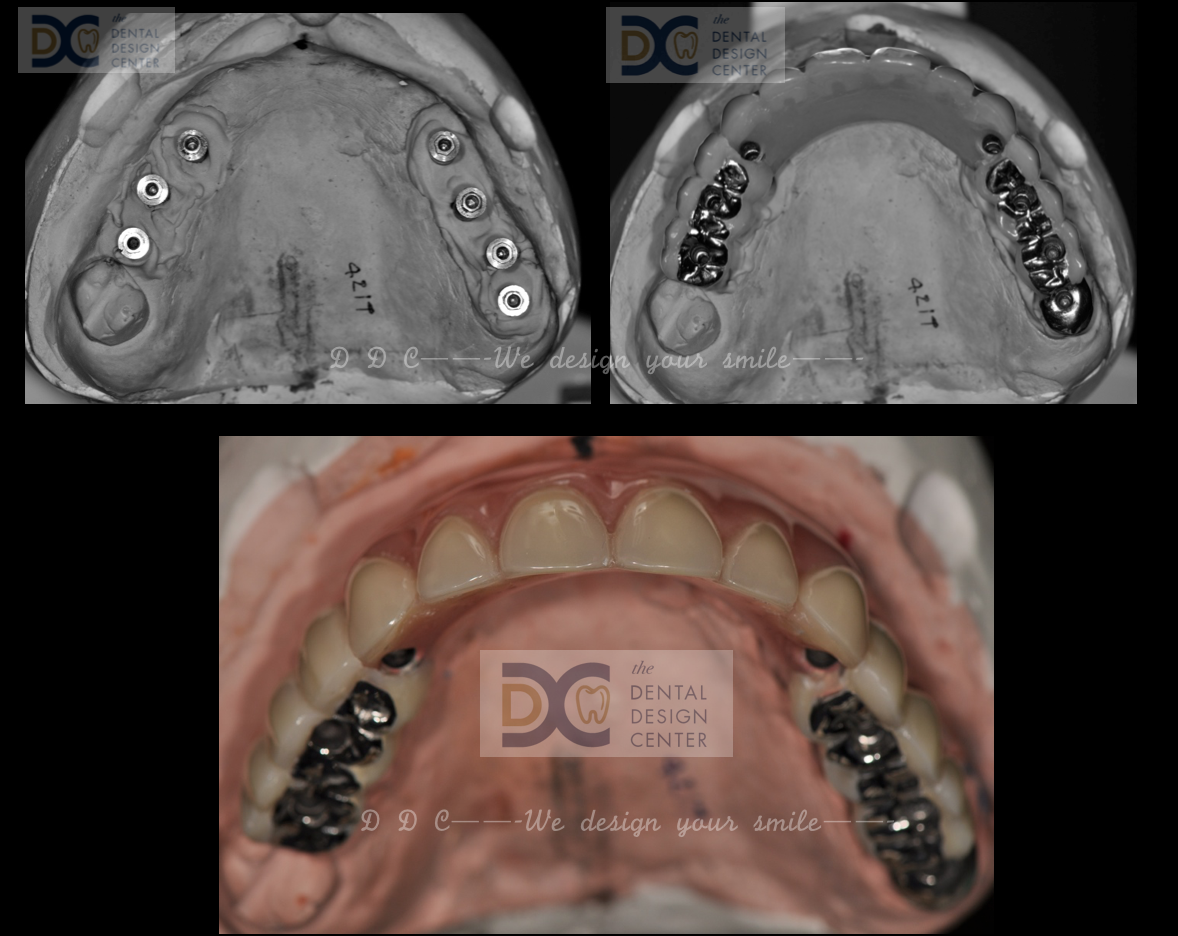

Picture shows the maxillary prosthesis fabricated in dental laboratory with the combination of metal framework and resin teeth

With inadequate posterior occlusal space, the prosthesis has occlusal metal design and buccal composite material veneering.

Pictures show the combination of composite/ acrylic resin teeth and the milled titanium metal framework; hybrid prosthesis design